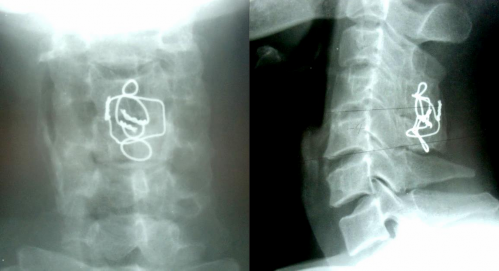

7 NĂM SAU

THẲNG NGHIÊNG

Sau mổ 7 năm: tình trạng chỉ KHX vẫn tốt. Liền xương độ I. Không di lệch thứ phát